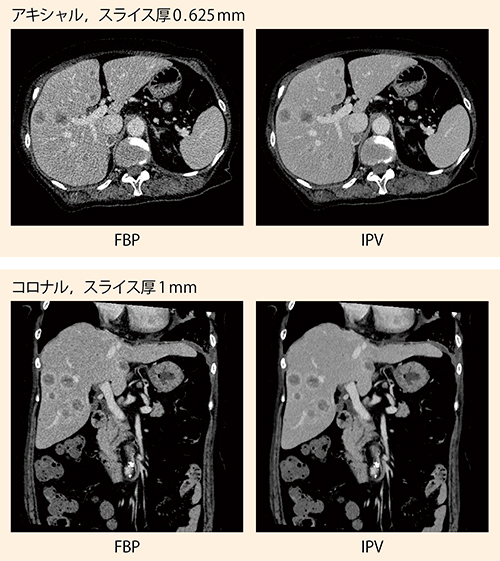

■SCENARIA Viewによる臨床画像

多発肝転移疑い,副腎転移疑い症例

CTDIvol:8.7mGy,DLP:456.7mGy・cm,100kV,420mgI/kg造影剤量を30%低減し,管電圧100kVにて撮影。IPVではFBPの質感を保ったまま大幅なノイズ低減ができており,多発転移の小さな腫瘍のリング状濃染など,病変部や臓器の境界・連続性の視認性が向上している。